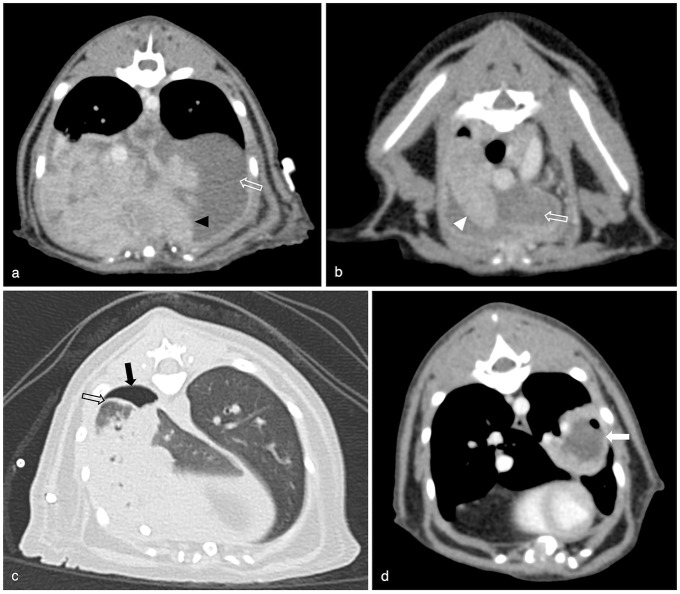

ObjectivesThe purpose of this retrospective, descriptive study was to assess CT findings and short-term outcome of cats with pyothorax presented to a referral hospital.MethodsThoracic CT studies of 41 cats with pyothorax comprising pre-contrast lung and soft tissue reconstructions and post-contrast soft tissue reconstructions were blindly reviewed by two European College of Veterinary Diagnostic Imaging (ECVDI) board-certified radiologists and a third-year ECVDI resident, referencing a predetermined list of imaging features. Clinical outcomes, including treatment options, survival to discharge and length of hospitalisation, were recorded.ResultsAll cats (100%) had pleural effusion. Common imaging findings included intrathoracic lymphadenomegaly (85%), pleural thickening (85%), presence of pannus (81%) and evidence of pneumonia (49%). Pulmonary abscessation was suspected in 22% of cats and foreign bodies in 12%. Of the 41 cats, 20 were managed medically, 20 underwent surgery and one had unsuccessful medical treatment followed by surgical intervention. The median duration of hospitalisation was 7 days, and 36 cats survived to discharge.Conclusions and relevanceThis study demonstrates that cats with pyothorax commonly have marked changes on CT that involve multiple thoracic compartments. Our study population highlights that feline pyothorax can have a good short-term outcome when managed either medically or surgically.

Abstract Image